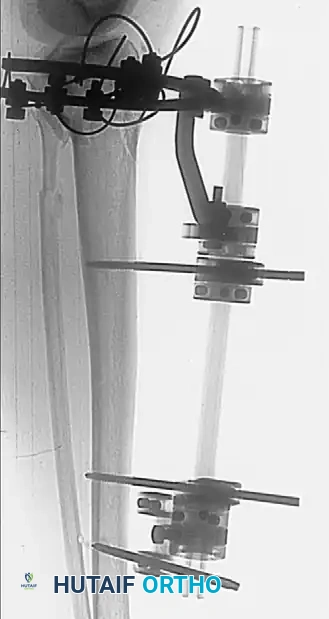

Definitive External Fixation

When soft tissue conditions preclude internal fixation entirely, or in highly contaminated open fractures, definitive treatment with external fixation is indicated. Minimal soft tissue dissection is required, drastically reducing the risk of iatrogenic devascularization and deep infection.

Ring and Wire Fixation (Ilizarov Method):

Clinical studies demonstrate that fine-wire circular fixators yield 87% to 88% good or excellent functional results in complex plateau fractures, with superficial pin tract infections occurring in only 6.5% to 12% of cases. A properly tensioned four-wire construct provides biomechanical stability comparable to dual plating.

In a series of 57 patients with Schatzker type VI fractures treated with Ilizarov fixation (38% of which were open fractures), acceptable reductions yielded an average knee ROM of 115 degrees.

Surgical Warning: Anatomical studies confirm that the knee joint capsule reflects distally up to 14 mm below the articular margin. To prevent the catastrophic complication of septic arthritis tracking from a superficial pin site, all wires and half-pins must be placed strictly extra-capsularly—at least 14 mm distal to the joint line.

Hybrid and Monolateral Fixation:

Monolateral half-pin external fixators or hybrid frames (combining a proximal tensioned wire ring with distal diaphyseal half-pins) offer alternative solutions. These frames are technically less demanding to apply than full Ilizarov frames and allow excellent access for wound care. Accessory percutaneous cancellous screws are frequently utilized in conjunction with the frame to compress and maintain the articular reduction, while the frame neutralizes bending and torsional forces across the metaphyseal-diaphyseal junction.